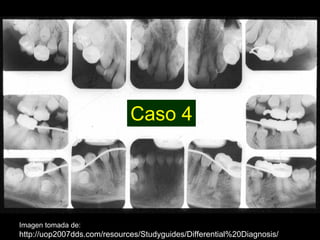

Dentinogénesis imperfecta es una condición genética que causa un disturbio en la formación de la dentina. Existen tres tipos principales. El tipo I se asocia con osteogénesis imperfecta. El tipo II solo afecta la dentina y causa dientes amarillos o grises con atrición. El tipo III es raro y se encuentra en un área aislada de Maryland, con exposiciones pulpares frecuentes. Todos los tipos muestran características radiográficas como obliteración de cámaras y conductos,